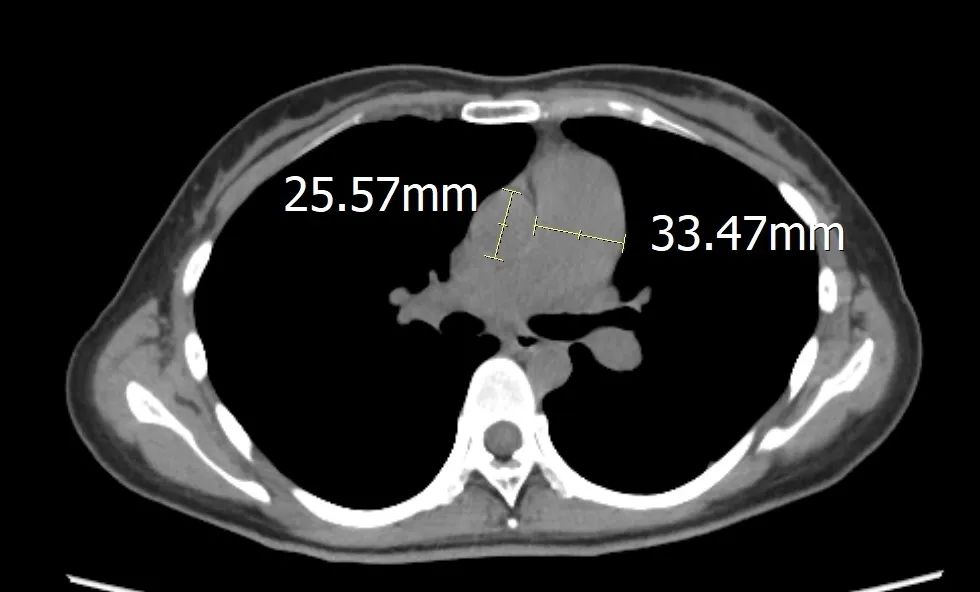

为了寻求更明确的病因和更具针对性的治疗方案,王女士和家人在了解到昆明市延安医院在心血管疑难病症诊治及精准医学应用方面的能力后,毅然决定前来就诊。接诊时,患者王女士的症状非常典型。她稍作活动便会感到明显的呼吸困难和心慌,爬5楼都会有明显症状,严重影响了她的日常活动能力。面对这样的患者,戴海龙医生团队在详细了解病史和病情后,迅速展开了深入分析。考虑到王女士年纪轻、病情重,且常规检查未能明确病因,戴海龙医生高度怀疑其背后存在遗传学因素。

肺动脉高压是一种以肺动脉压力异常升高为特征的恶性心血管疾病,被称为“心血管疾病中的癌症”。许多被诊断为“特发性”的肺动脉高压,尤其是那些年纪轻轻就发病的患者,其背后往往隐藏着遗传因素。BMPR2基因是最常见的致病基因之一。当一个年轻人被诊断为原因不明的肺动脉高压时,基因检测可以帮助医生明确诊断、制定治疗方案,更科学地预测疾病的未来走向,为患者及其家人的生育、健康规划提供科学依据,实现对疾病的家族性预防。